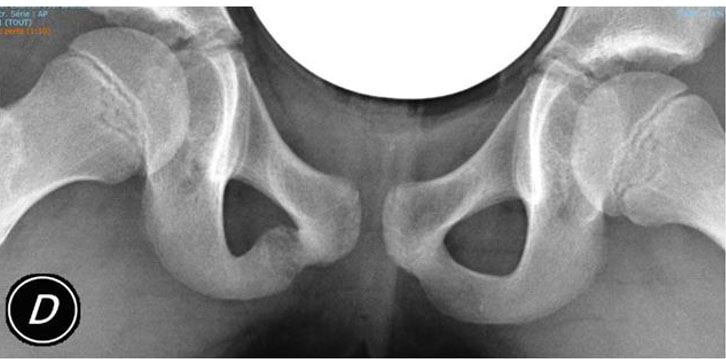

Anteroposterior radiographs of the pelvis showed symmetric enlarged IPS with a focal moderate area of demineralization of the right IPS.

Figure 1: Anteroposterior radiograph of the pelvis demonstrating an asymmetric enlargement of the right ischiopubic synchondrosis (IPS) with a focal area of osteolysis.